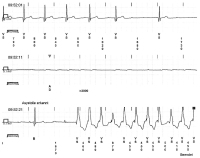

AV-Block

Abbildung 3: 11 Sekunden Pause bei intermittierendem AV-Block III mit kurzer nicht anhaltender ventrikulärer Tachykardie (nsVT)

Keywords: intermittierender AV-Block III